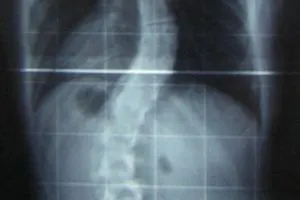

scoliosis_x_ray_200_300.jpg

Scoliosis is a condition in which the spinal column appears curved rather than straight when viewed from the back. Symptoms include pain, restricted upper body movement and, in more severe cases, increased pressure on the heart and lungs. The misalignment of the vertebrae that is associated with scoliosis tends to worsen with age due to an asymmetric degeneration of the spine that is produced by the abnormal curvature. This means that effective early management of the condition is important. As yet, however, there have been few published studies of exercise and rehabilitation programs specifically designed to help patients with scoliosis.